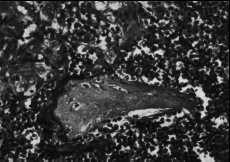

Эпителиальный покров. При гистологическом исследовании препаратов всех групп были выявлены изменения со стороны эпителиального покрова. Они более выражены в лакунах, меньше на зевной поверхности и зависели в значительной мере от длины и ветвистости крипт. Принято, что признаком хронического тонзиллита является значительная ретикуляция эпителия, т.е. разрастание ретикулярной сети в эпителии и обильную инфильтрацию ее лимфоцитами и плазматическими клетками. В наших наблюдениях при токсическом зобе инфильтрация лимфоцитами достигала такой степени, что граница между эпителием и подлежащей тканью перестает определяться (рис.1,2). В некоторых наблюдениях в эпителиальном покрове обнаруживались единичные полиморфноядерные лейкоциты в эпителии крипт, а также папиллярные выросты стенок крипт (рис.3), закрывающие их просвет и тем самым создающие условия для задержки содержимого крипт. Как известно, в развитии хронического тонзиллита .особое значение придается задержке отделяемого крипт. В результате наличия ветвистых извилистых крипт, папиллярных выростов, пробки приводят к сужению и даже полной облитерации устьев крипт (рис.4,5). Задержка со-держимого крипт в отдельных случаях обусловливает расширение их просвета (рис.6), а при полной облитерации некоторые авторы наблюдали образование ретенционных кист (рис.7).

Рис. 5. Полная облитерация полости крипт. Окраска гематоксилин-эозин, ув. х 400 |

Рис. 6. расширение полости крипт. Окраска гематоксилин-эозин, ув. х 400 |

Рис. 7. Киста в полости крипт. Окраска гематоксилин-эозин, ув. х 400